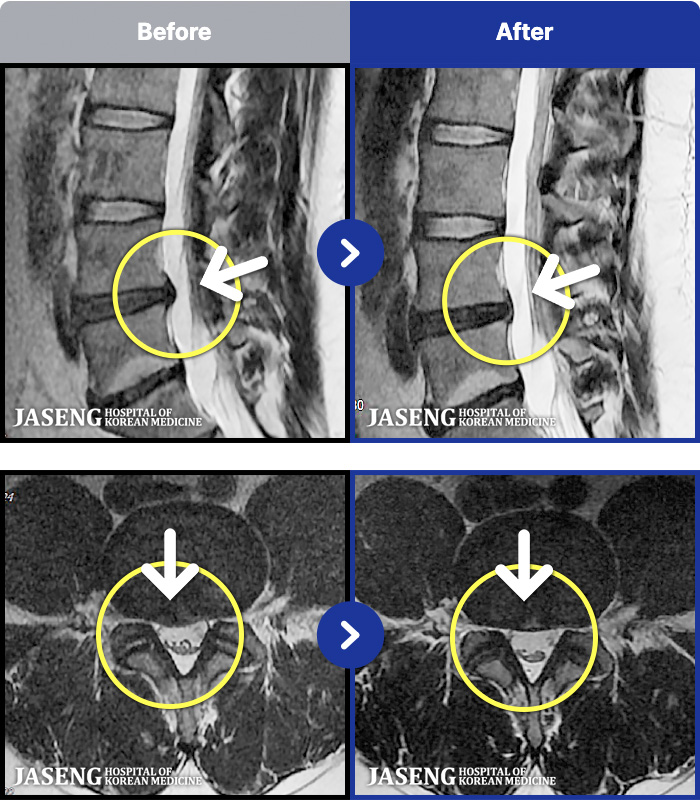

54 MRI ũ ʸ Ȯϼ.

ȯںп Ǹ ǿ ԿǾ, ο ġ ۿ Ƿ ġḦ Ͻñ ٶϴ.